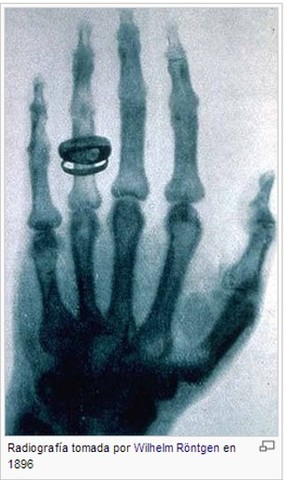

El 8 de noviembre de 1895 produjo radiación electromagnética en las longitudes de onda correspondiente a los actualmente llamados rayos X. En los años siguientes, Röntgen publicó unos estudios «sobre un nuevo tipo de rayos»